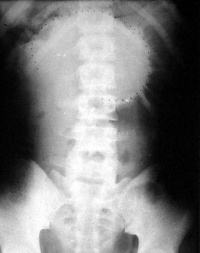

麻痹性肠梗阻

X线平片:见小肠、结肠均胀气明显。